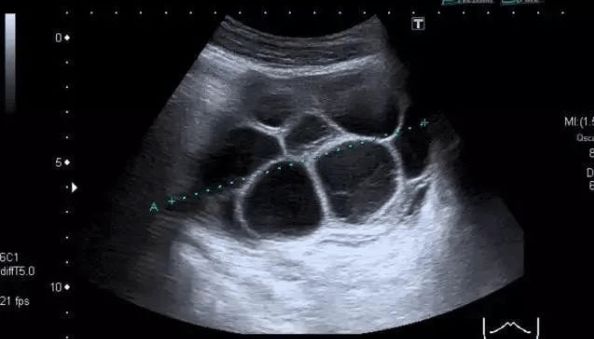

中度OHSS:除腹胀、腹部不适、恶性呕吐等症状外,卵巢增大到5-10cm,B超提示腹水。

重度OHSS:腹胀等临床症状明显加重,伴有大量腹水或者胸水,尿量减少。卵巢直径大于10cm。实验室指标出现明显的血液浓缩、凝血功能异常、肝肾功能异常等。